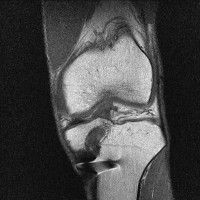

무릎 mri 간단히 봐주실 수 있으시나요 ㅠㅠ

안녕하세요 8년전 십자인대 수술하고 최근 무리한 운동에 무릎 불편감이 생겨서

mri 찍었습니다.

진단결과는 첫 찍은 병원에서 활액막염 이라는 진단을 받았습니다. 혹시 봐주실 수 있으실까요?

• 2번 째 사진

• 안녕하세요. 강성주 의사입니다.

올라온 MRI가 단편적이라서 정확한 진단에 어려움이 있지만 십자인대에는 큰 이상이 있지는 않은것 같으며, 무릎관절내 물이 있는 것으로 보아 활액막염의 진단이 맞을 것 같습니다.

하지만 단편적인 영상이기 때문에 촬영병원에서 정확한 판독지 등을 받으시는 것이 좋겠습니다.